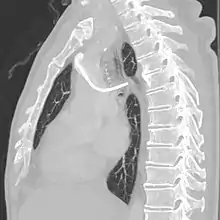

The port is usually inserted in the upper chest (known as a "chest port"), just below the clavicle or collar bone, with the catheter inserted into the jugular vein.

A port consists of a reservoir compartment (the portal) that has a silicone bubble for needle insertion (the septum), with an attached plastic tube (the catheter). The device is surgically inserted under the skin in the upper chest or in the arm and appears as a bump under the skin. It requires no special maintenance other than occasional flushing to keep clear. It is completely internal so swimming and bathing are not a problem. The catheter runs from the portal and is surgically inserted into a vein (usually the jugular vein or less optimally the subclavian vein). Ideally, the catheter terminates in the superior vena cava or the right atrium. This position allows infused agents to be spread throughout the body quickly and efficiently.

The port is then sutured on two sites to the underlying muscles. The tip of the catheter is checked for kinks and position using a fluoroscope. Besides that, aspiration of blood and contrast injection through the chemoport can also be used to confirm the position. The port is the closed in two layers (subcutaneous tissue is sutured first, followed by the skin). Sterile dressing is then placed on the port.[3] The optimum site to park the tip of the catheter is at the cavo-atrial junction or with margin of error of not more than 4 cm above the junction.[3]

The incidence of catheter fracture is 2.3%. The fracture can be due to "pinch-off syndrome" when the vein and the catheter is compressed when passes between the clavicle and first rib before turning 90 degrees into the superior vena cava. Fractured catheter component can dislodge most commonly into pulmonary arteries (35%), right atrium (27%), right ventricle (22%), and superior vena cava and peripheral veins (15.4%).[5]

Malpositioning of the catheter happens in 0.1 to 5.6% of the time. This can be due to malposition within or outside the superior vena cava. Causes includes: unexpected branches of the veins, vessel angulations, vein stenosis or venous tortousity.[5]